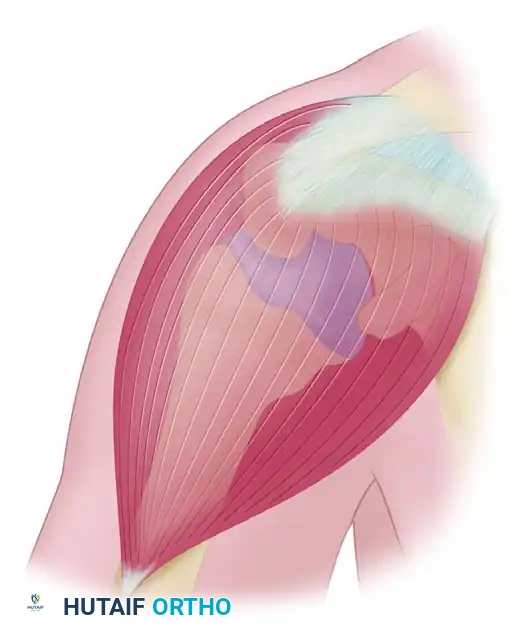

In 1972, Charles Neer introduced the modern concept of impingement syndrome. He characterized it as a mechanical conflict caused by a ridge of proliferative spurs and excrescences on the undersurface of the anterior process of the acromion. This abutment is exacerbated by repeated impingement of the rotator cuff and the humeral head against the coracoacromial arch during forward elevation and internal rotation.

Figure 46-3: Impingement syndrome. The supraspinatus tendon is visualized passing directly beneath the rigid coracoacromial arch, highlighting the anatomical bottleneck susceptible to mechanical compression.

Neer identified that the anterior third of the acromion and its anterior lip were the primary offending structures. He subsequently introduced the concept of a pathological continuum, categorizing impingement syndrome into three distinct developmental stages.